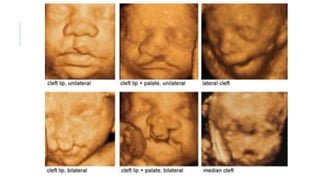

A. Normal. B. Labio hendido unilateral que se extiende hacia la nariz. C. Fisura

unilateral que afecta labio y maxilar y se extiende hacia el agujero incisivo. D. Fisura

bilateral que afecta labio y maxilar. E. Fisura palatina aislada. F. Fisura palatina

A. Normal. B.Labio hendido unilateral que se extiende hacia la nariz. C. Fisura unilateral que afecta labio y maxilar y se extiende hacia el agujero incisivo. D. Fisura bilateral que afecta labio y maxilar. E. Fisura palatina aislada. F. Fisura palatina